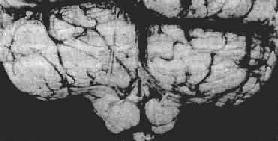

图16-7 海马钩回疝

左海马回内侧肿胀有深切迹(箭头),中脑右移变形,中脑右大脑脚受压,局部坏死出血(Kemohan切迹)